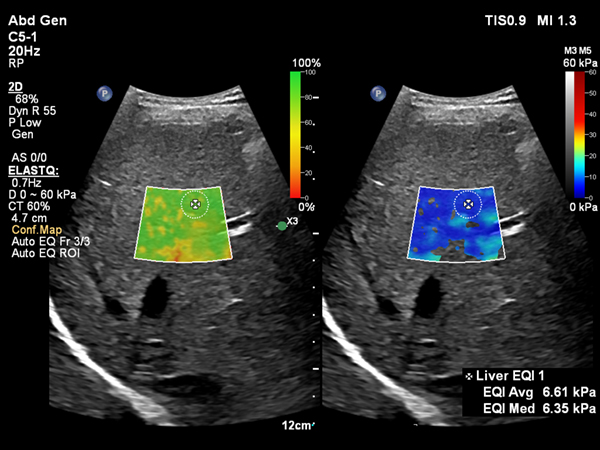

Shear Wave Elastographyを使用して肝臓の硬さを非侵襲的に計測するアプリケーションElastQに,自動化機能が追加されました。Auto ElastQは、計測に適したフレームやROIポジションを自動で判別し,計測結果を表示することが可能です。これにより,これまで課題であった検査時間を最大60%短縮し3,99%の再現性が報告されています。4